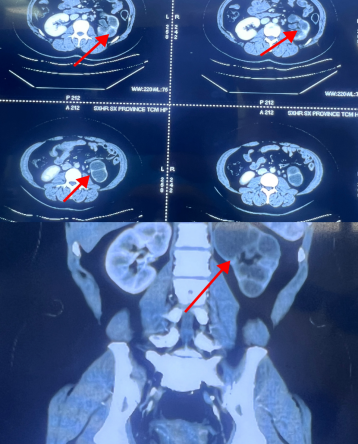

患者长期饱受反复腰痛、尿路感染困扰,被诊断为“肾积水”,多方治疗后效果不佳,陕西省中医医院泌尿外科张旭主任接诊并将其收住入院。入院后,张旭主任迅速组织全科开展病例讨论,凭借丰富的临床经验及对感染性疾病的深入研究,结合详细的影像学特征与实验室检查结果,精准锁定病因——肾结核合并无功能肾。随后,通过多学科会诊及结核特异性检测进一步验证,明确诊断,为后续治疗奠定基础。

患侧肾造影剂无显影